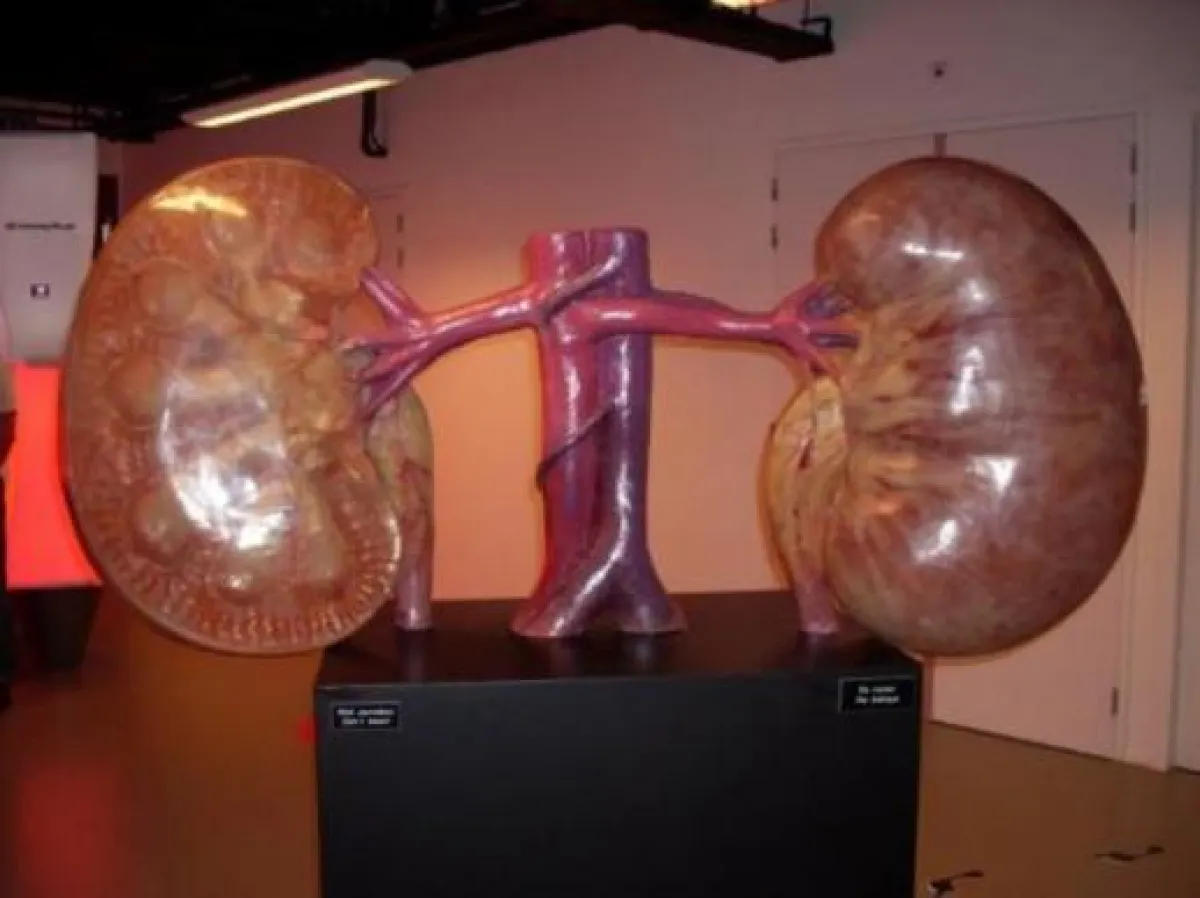

ويكشف عرضه التفاعلي أعضاء جسم الإنسان كافّة، بالصوت والصورة والمجسّمات.